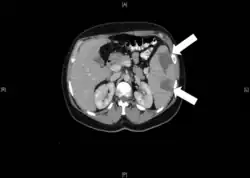

- Клиновидная форма. Специфична для селезёнки, почки, лёгкого.